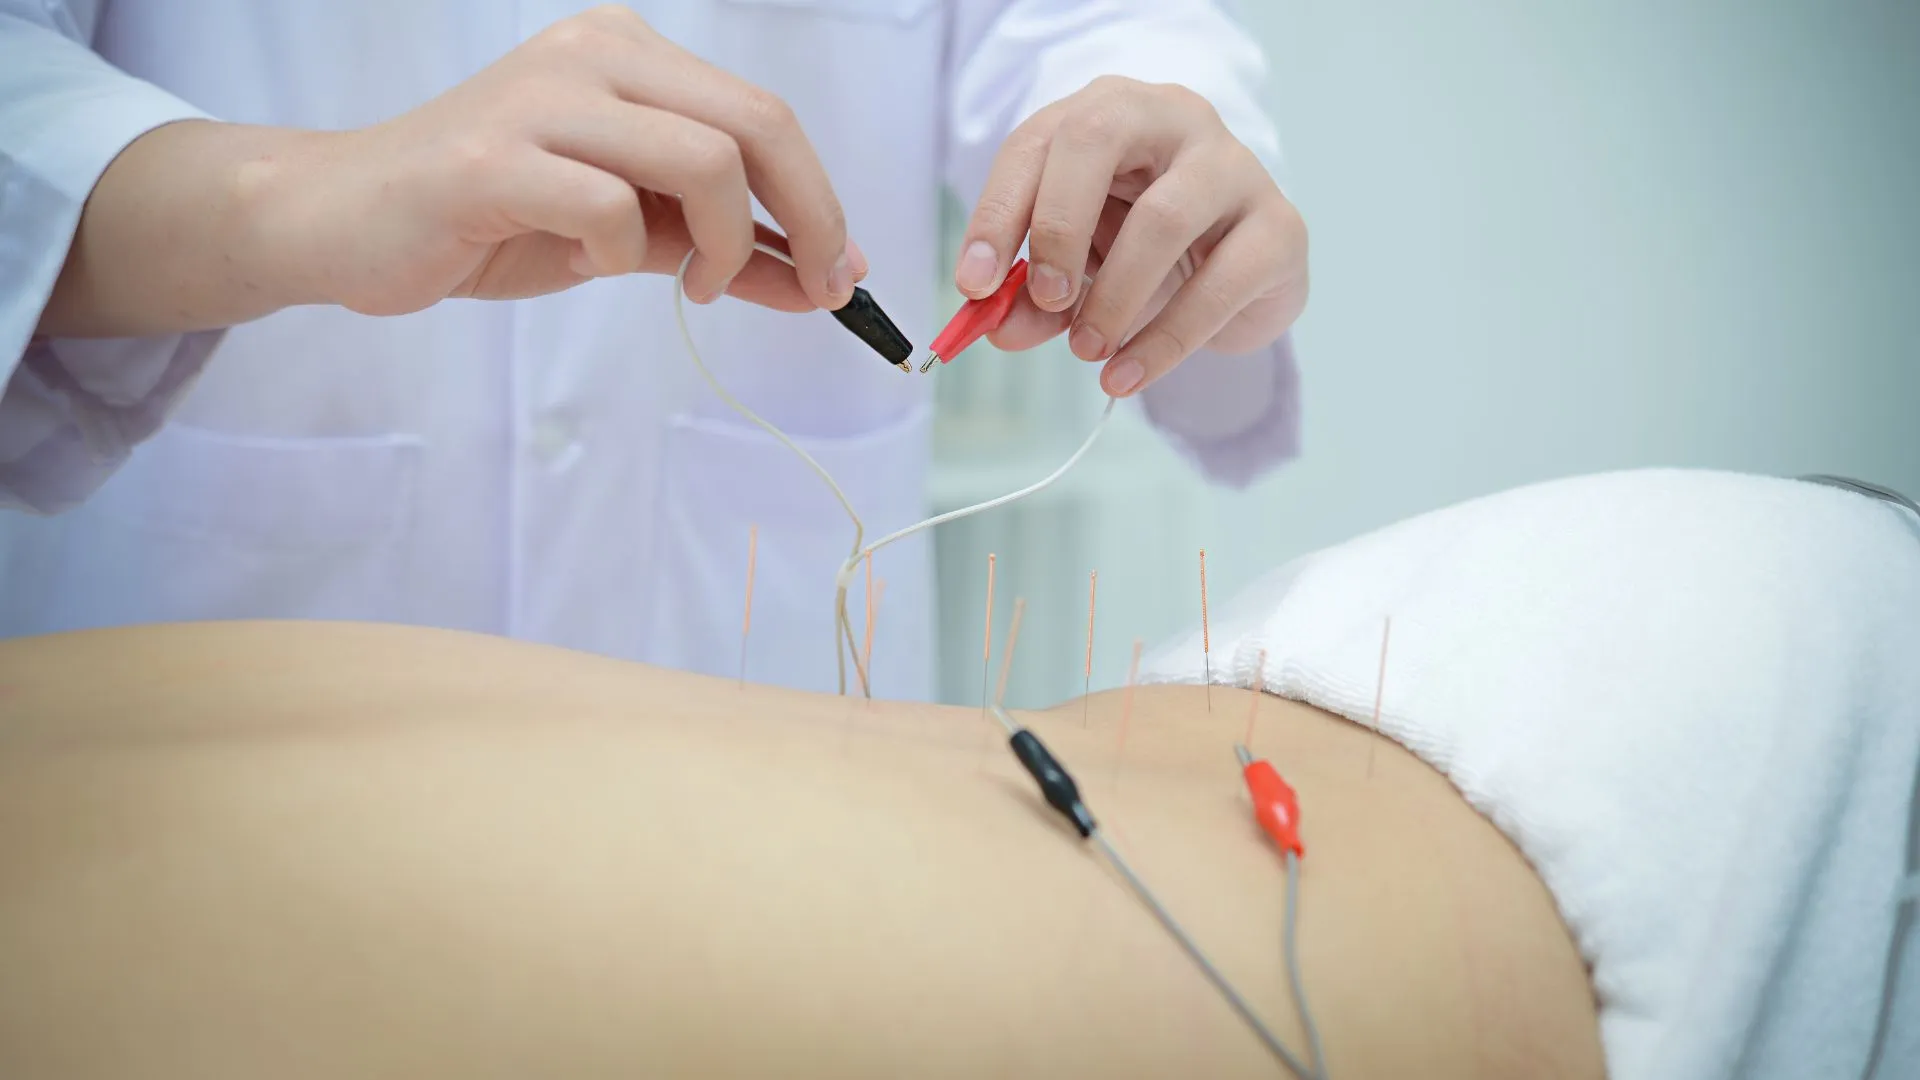

Osteopathy and Acupuncture Treatment for lower back pain

Osteopathy and Acupuncture Treatment are two of the most popular treatments for lower back pain. Osteopathy is a hands-on manual approach that focuses on the musculoskeletal system, which is designed to treat and prevent musculoskeletal pain. It involves manipulating joints, muscles, and soft tissue to improve mobility and reduce pain. Acupuncture is also an effective treatment option for lower back pain. It works by stimulating certain points in the body to reduce inflammation and pain. This ancient Chinese technique has been used for centuries and can be very effective in relieving lower back pain. Both treatments have their own advantages and disadvantages; however, they can both provide relief from lower back pain when used properly. They should always be discussed with your doctor before beginning any treatment plan.